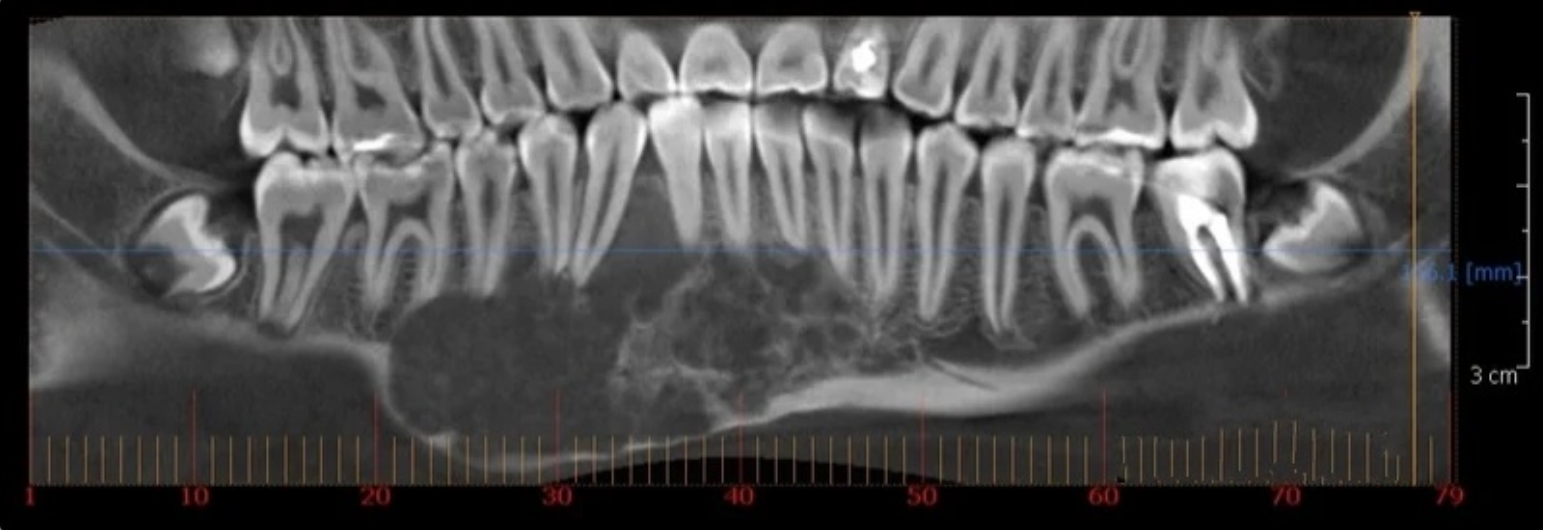

Рис.1. Результаты рентгенологического исследования (компьютерная томография с 3D-реконструкцией изображения). Плоскостной фронтальный срез нижней челюсти.

Рис.2 Результаты рентгенологического исследования (компьютерная томография с 3D-реконструкцией изображения). Плоскостные срезы нижней челюсти, в проекции расположения опухолевидного образования.

При анализе рентгенограмм определяется очаг деструкции костной ткани альвеолярной части и тела нижней челюсти овальной формы, по типу вздутия кости с крупноячеистым рисунком, вытянутый вдоль горизонтальной оси тела нижней челюсти, в проекции расположения 46, 45, 44, 43, 42, 41, 31, 32, 33, 34 зубов. Чёткость границ очага деструкции от неповреждённой кости определяется не со всех сторон. Внутри очага отмечается наличие множества мелких полостей или ячеистых образований более крупных размеров, отделённых друг от друга костными перегородками различной толщины.

Кортикальный слой неравномерно истончён, волнистый, местами полностью резорбирован и разрушен. Корни 45, 44, 43, 42, 41, 31, 32, 33 зубов веерообразно отклонены от центральной оси в обе стороны от центра вздутия.

Периодонтальные щели у вышеуказанных зубов не прослеживаются.

Нижнечелюстной канал не визуализируется.